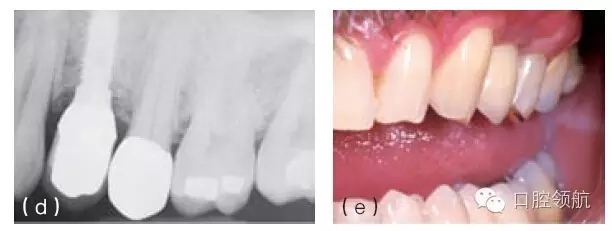

圖10.3 種植體位置靠遠(yuǎn)中,嘗試使用個(gè)性化基臺(tái)糾正植入位置的偏差。但是由于種植體位置過于靠遠(yuǎn)中,基臺(tái)的頸部位于鄰近磨牙鄰面接觸區(qū)以下。這個(gè)位置將阻礙修復(fù)體在基臺(tái)上就位,同時(shí)單冠的近中會(huì)出現(xiàn)懸突。需要取出種植體,并在缺牙區(qū)近遠(yuǎn)中向的中心區(qū)重新植入新的種植體。